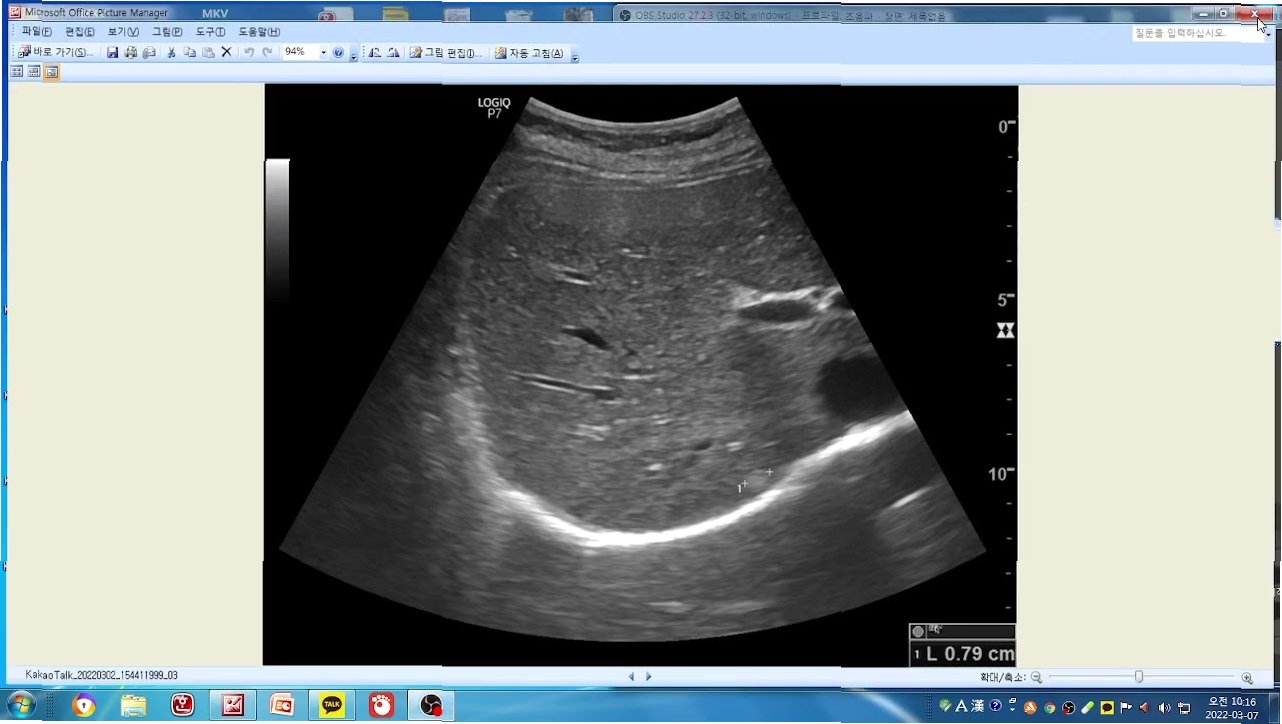

간혈관종, 예상치 못한 진단

슈의 건강검진 결과, 간에서 종양이 발견되었고 전문의는 '간혈관종'이라는 진단을 내렸습니다. 간혈관종은 간에 생기는 양성 종양으로, 대부분 증상이 없지만 크기가 커지면 복통, 소화불량 등을 유발할 수 있습니다. 슈는 예상치 못한 진단에 당혹감을 감추지 못했지만, 앞으로 건강 관리에 더욱 힘쓸 것을 다짐했습니다. 이번 방송을 통해 슈는 간혈관종에 대한 정보와 함께, 건강 관리에 대한 중요성을 강조하며 시청자들에게 건강한 삶을 위한 메시지를 전달할 것입니다. 슈의 건강 회복을 위한 노력과 앞으로의 활동에 많은 관심과 응원이 쏟아질 것으로 예상됩니다.